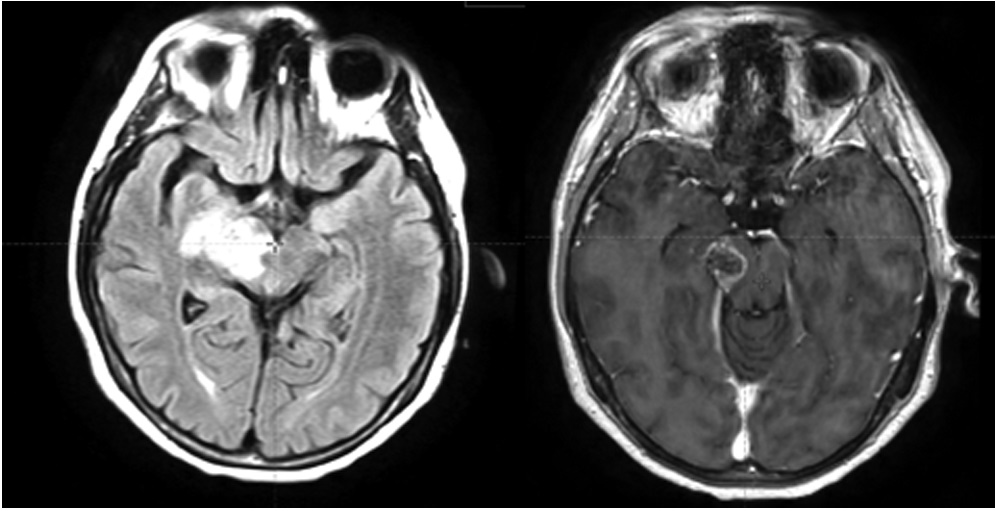

В радиотерапевтическое отделение № 1/дневной стационар БУЗ ВО «ВОНКОЦ» поступила на лечение пациентка 1977 г. р. с диагнозом: глиома grade 4 правого таламуса, заднего бедра внутренней капсулы, правой ножки мозга. На протяжении 3 месяцев пациентка отмечала прогрессирующую слабость в левой руке и ноге, нарушение координации движений, приступы панического страха. Гистологическое исследование операционного материала не проводилось, т. к. в соответствии с заключением онкоконсилиума в НМИЦ нейрохирургии им. Н. Н. Бурденко проведение стереотаксической биопсии сопряжено с высоким риском развития тяжелых неврологических осложнений: параличи и парезы, бульбарный синдром (расстройства дыхания, глотания, сердечной деятельности, тонуса сосудов), нарушение речи, летальный исход. Было принято решение провести лечение без хирургической верификации и расценить опухоль как глиобластому (глиому grade 4) по клинико-рентгенологическим данным. По данным МРТ головного мозга определяются МР-признаки внутримозгового солидного образования правой гемисферы головного мозга, вовлекающего ножку мозга, таламус, тело и хвост хвостатого ядра, наиболее вероятно, злокачественного генеза (рис. 1). Представленные МРТ-исследования выполнялись в отделении лучевой диагностики БУЗ ВО «ВОНКОЦ» на аппаратах: магнитно-резонансный томограф Philips Ingenia 1.5T и Philips Ingeniа Аmbition 1,5 Т.

Рисунок 1. МРТ головного мозга: импульсные последовательности T2 Flair и T1 с контрастированием

Figure 1. Brain MRI: T2 Flair and T1 pulse sequences with contrast